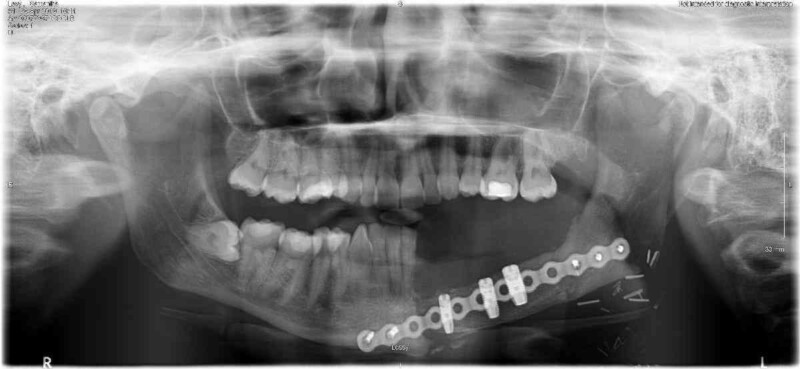

But her worst ordeal was yet to come. During the 11-and-a-half hour marathon June 2018 procedure, bone was cut from her hip and used to rebuild her jaw along with a metal plate. She also had muscles taken from her stomach to replace part of the gum. Doctors had to make a model of her hip and jaw to plan the surgery.

Sam had a final operation in May 2019 to remove the metal plate that held her face in place along the jawline. She said: “I’ve got it at home in a jar! It’s like a badge of honour.”